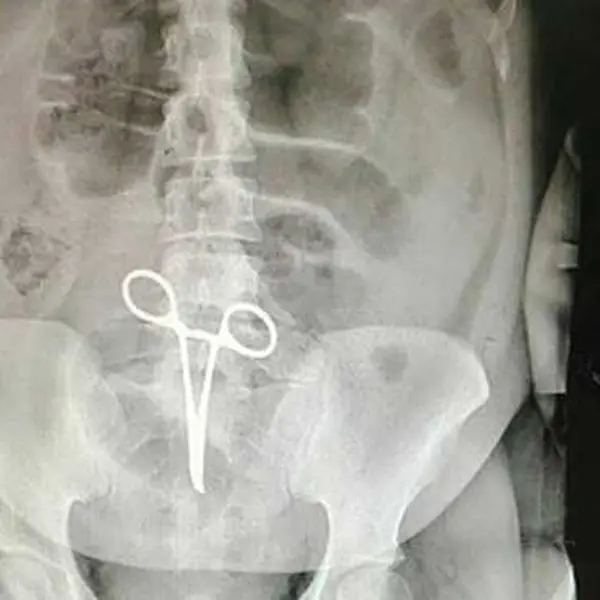

عذرخواهی رییس بیمارستان اردستان به خاطر پنسی که در شکم بیمار جا ماند / عکس

وی بابیان اینکه اشتباه رخ داده یکی از موارد نادر پزشکی بود که تاکنون در این بیمارستان اتفاق نیفتاده بود، افزود: بعد از اینکه عکس از ناحیه شکم بیمار گرفته میشود همکاران متوجه جسم خارجی(پنس) در داخل شکم بیمار میشوند.

رئیس بیمارستان شهید بهشتی اردستان، ادامه داد: بدون هیچ فوت وقتی مقدمات عمل جراحی سوم انجام میشود و عمل جراحی و عملیات بیرون آوردن پنس توسط پزشک جراح که این بیمار را عمل کرد انجام میشود.